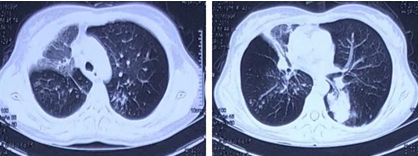

第10天复查胸部CT:右肺上叶空洞较前明显吸收,右肺中叶实变较前缩小(图3)。虽然患者呼吸困难明显减轻,肺部病变明显吸收,但复查CEA水平继续升高,遂行CT引导下肺穿刺活检并复查胸部CT(图4),病理回报光镜下可见梭形细胞增生,纤维组织增生伴慢性炎,间质呈机化性改变。鉴于临床症状、实验室检查及肺部影像学改善,考虑肺部感染的经验性治疗有效,遂安排转回当地治疗。

图片

图3  患者胸部CT

图4  患者胸部CT